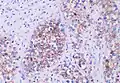

| Histopathology of classical seminoma, with typical features.[1] | |

Microscopic examination shows that seminomas are usually composed of either a sheet-like or lobular pattern of cells with a fibrous stromal network. The fibrous septa almost always contain focal lymphocyte inclusions, and granulomas are sometimes seen. The tumour cells themselves typically have abundant clear to pale pink cytoplasm containing abundant glycogen, which is demonstrable with a periodic acid-Schiff (PAS) stain. The nuclei are prominent and usually contain one or two large nucleoli, and have prominent nuclear membranes. Foci of syncytiotrophoblastic cells may be present in varied amounts. The adjacent testicular tissue commonly shows intratubular germ cell neoplasia, and may also show variable spermatocytic maturation arrest.[5]

The germ cell markers OCT 3/4 and CD117 (positive immunohistochemistry pictured) are useful for diagnosis.[10]